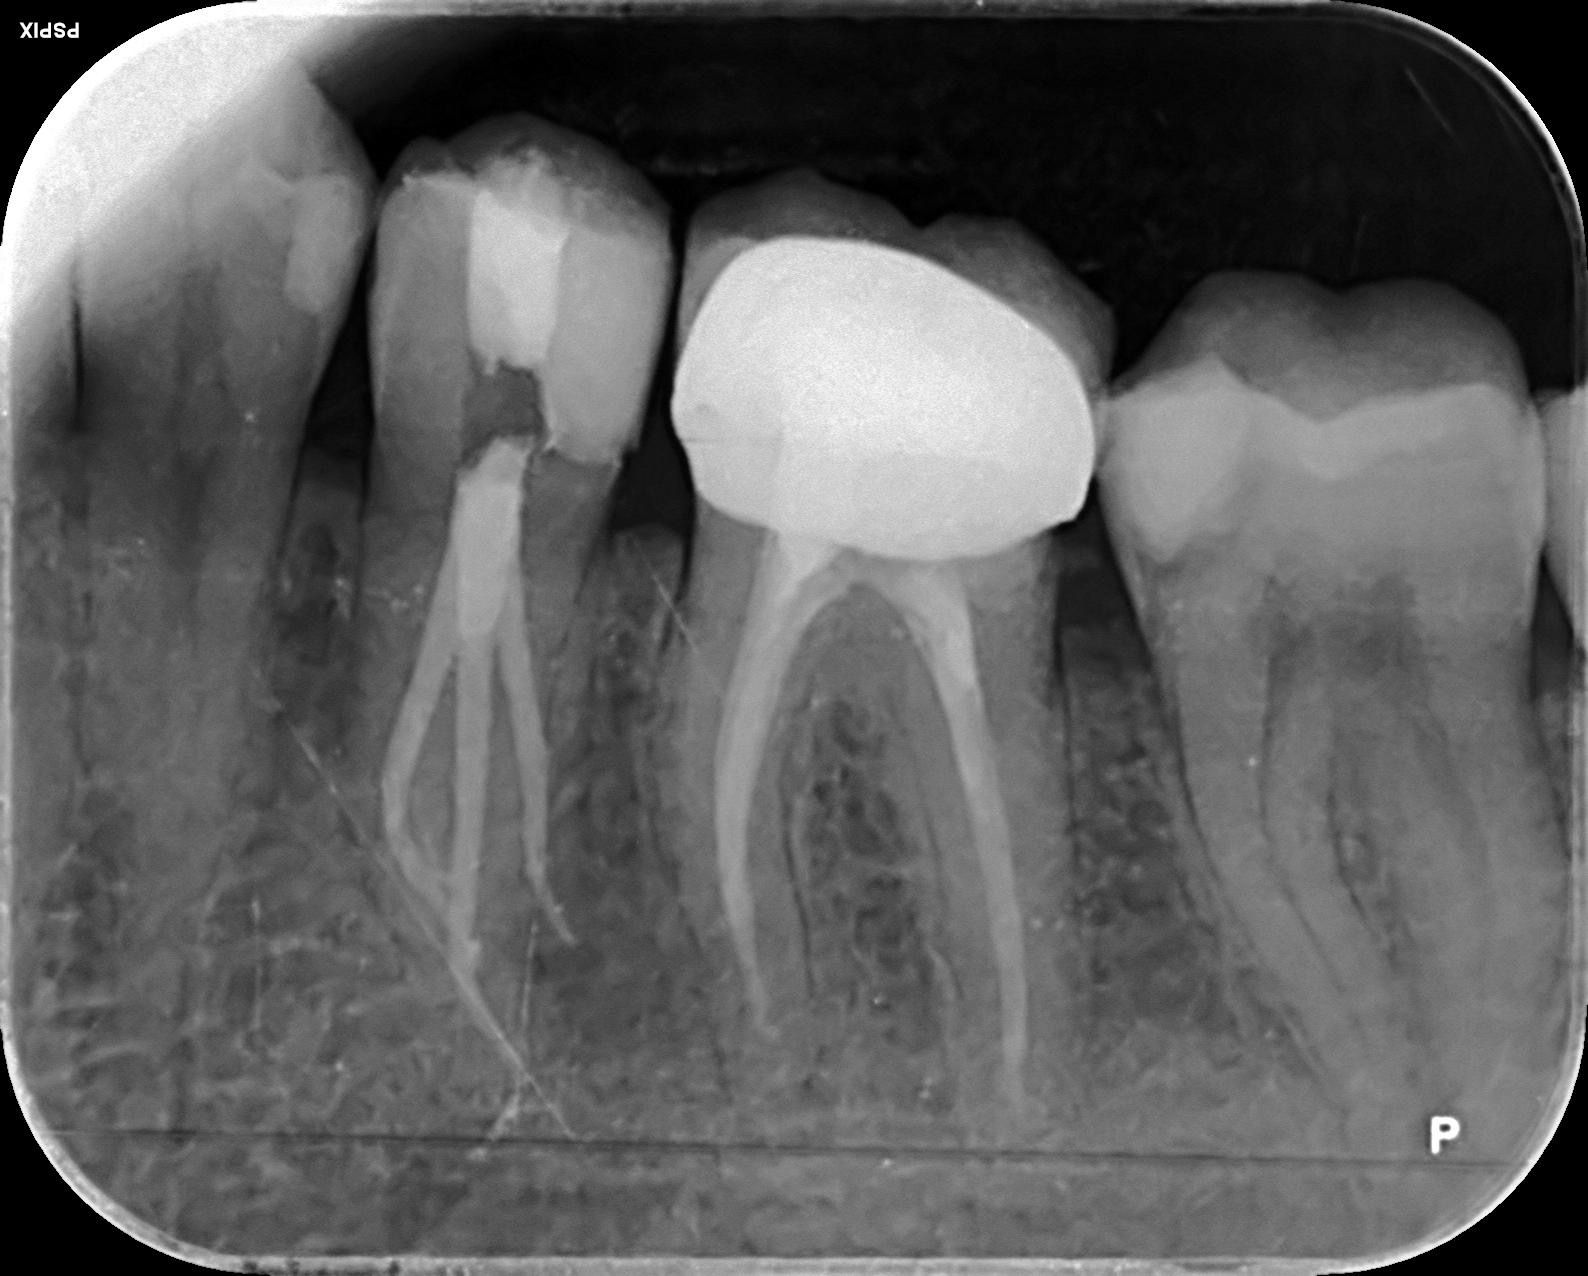

Casos clínicos realizados por la Dra. María Medina

Antes

Déspues

Caso 1